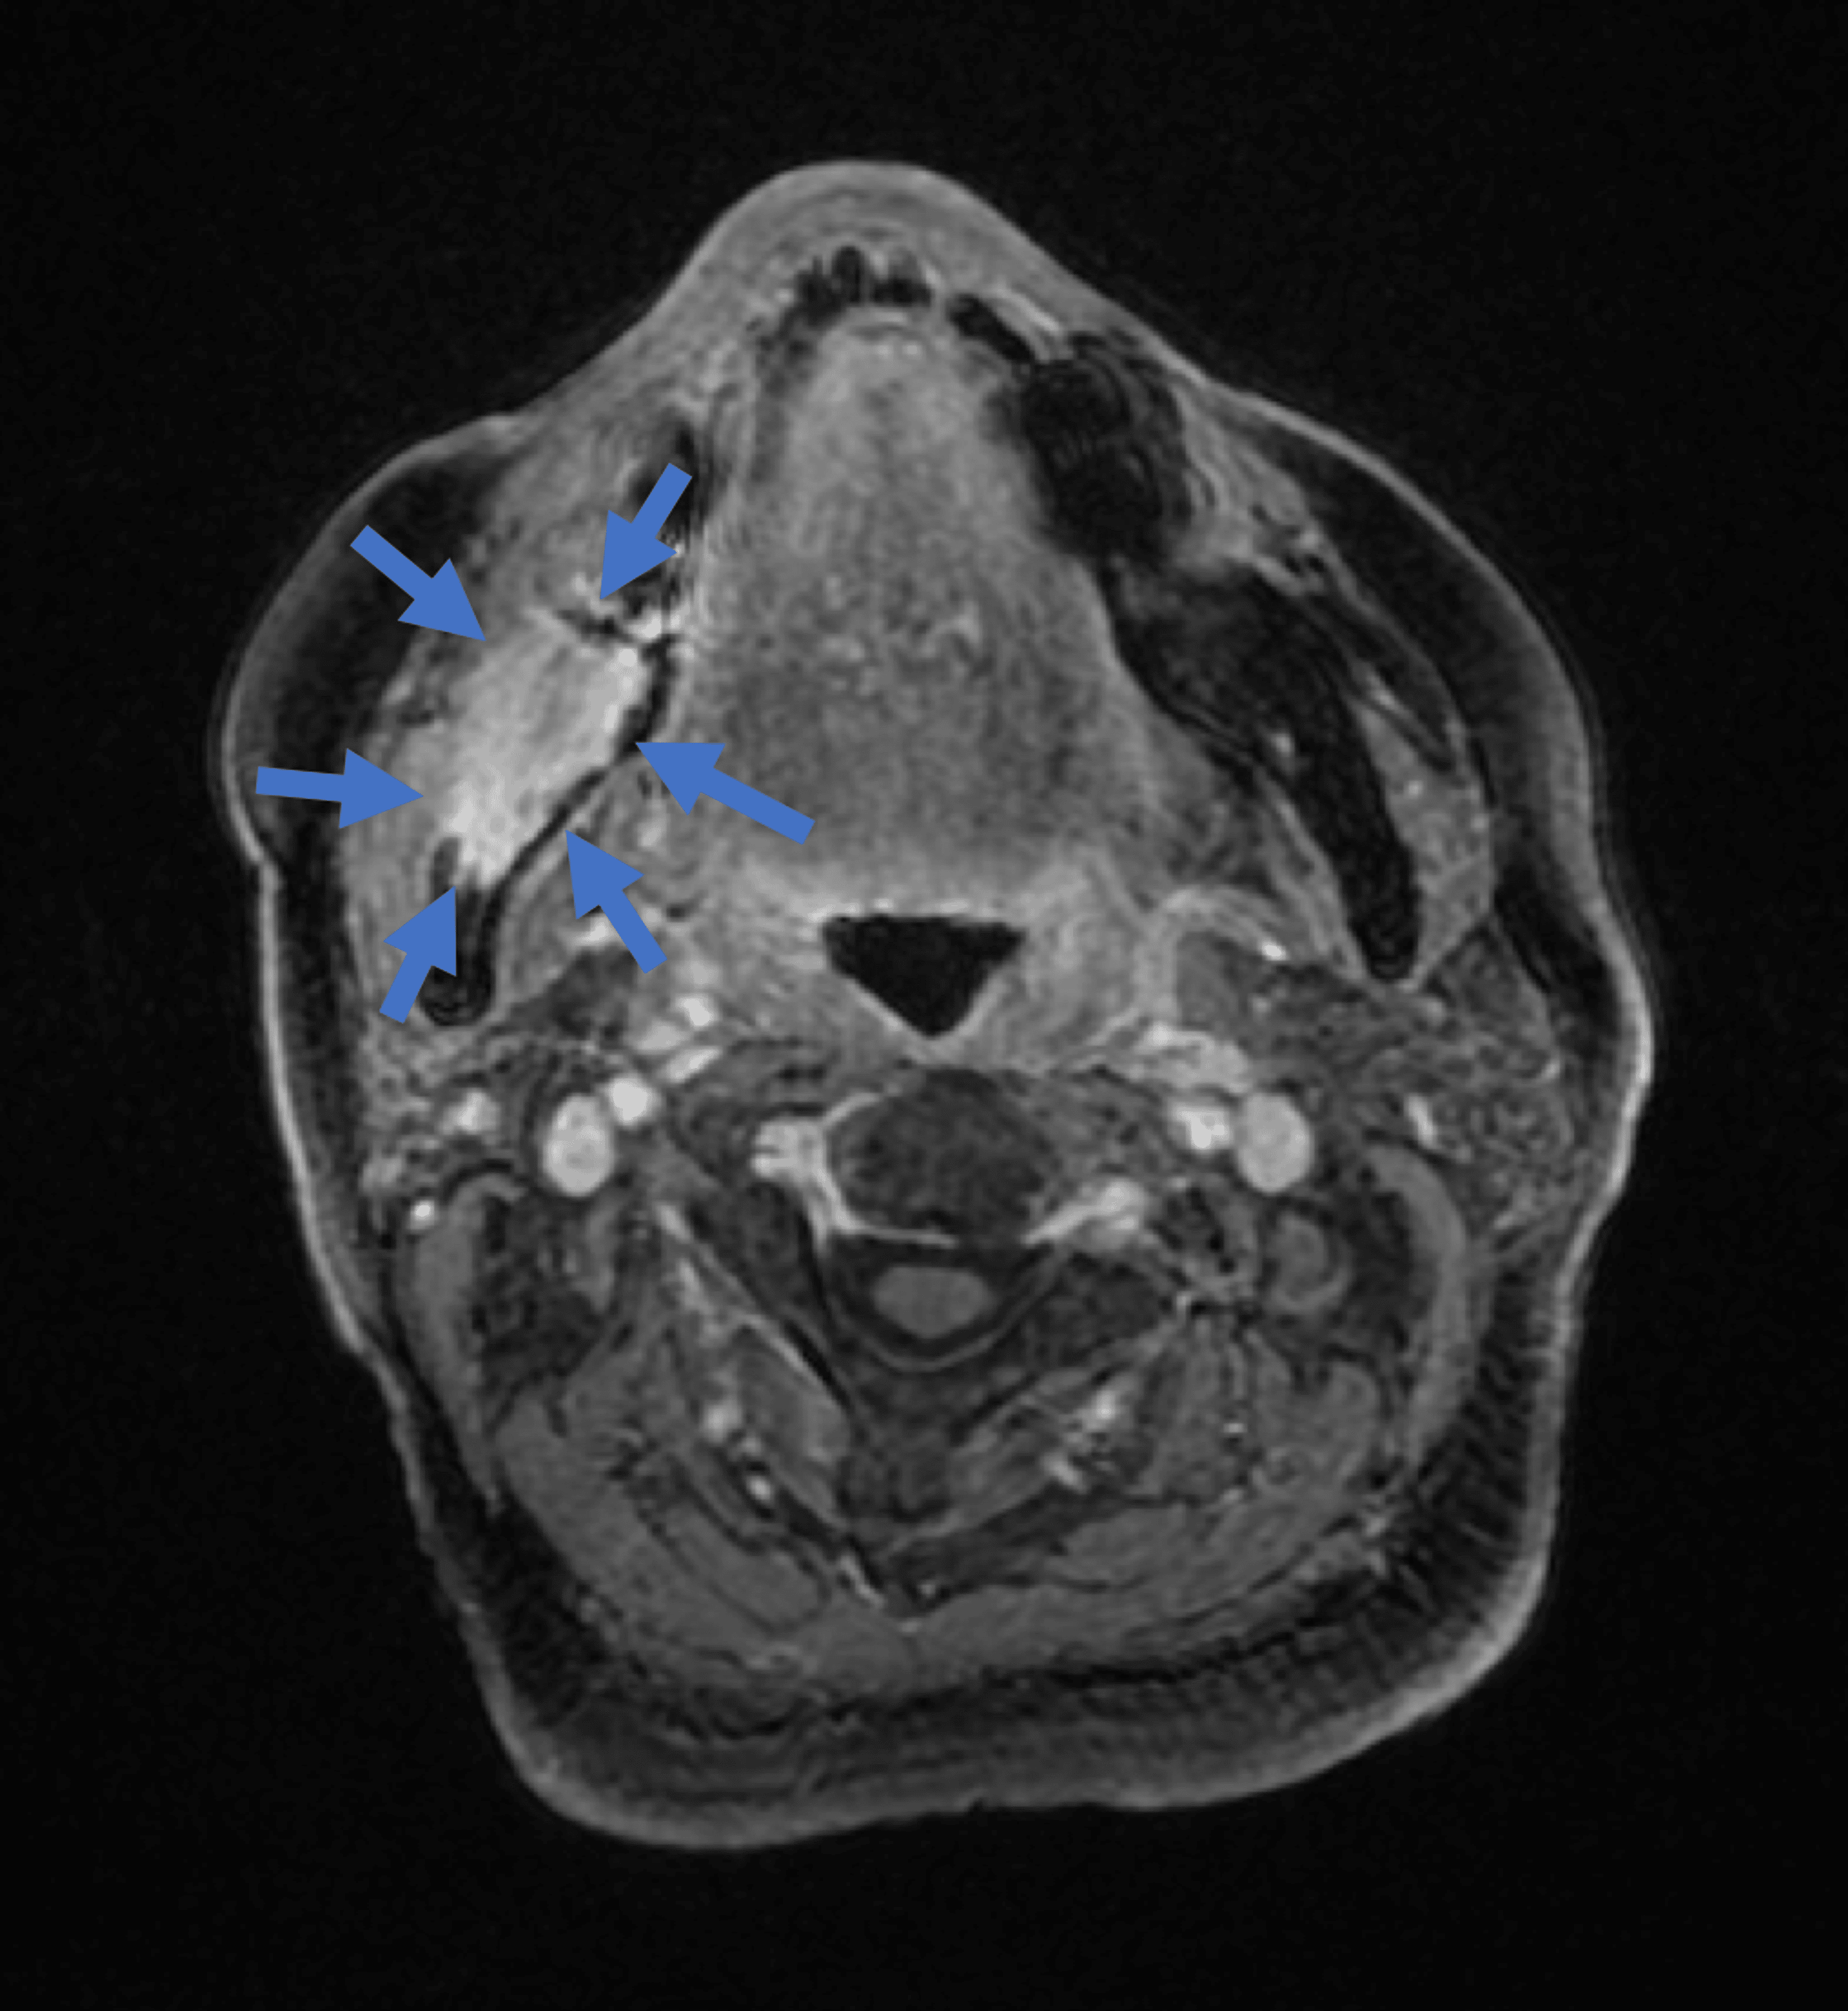

Spindle cell in a 64 years old male patient. Axial CT images... Download Scientific Spindle-Cell Sarcoma Jaw This diagnosis includes fibrosarcoma and sarcomas with indeterminate histomorphology, excluding melanocytic tumors and sarcomas that can be differentiated by histomorphology. Spindle cell carcinoma (scc) is a rare variant of squamous cell carcinoma characterized by elongated and pleomorphic. Spindle cell sarcoma (scs) is a malignancy, with the most recent surveillance, epidemiology, and end results (seer) data citing a total of 250. Spindle-Cell Sarcoma Jaw.

A Case of Spindle Cell Squamous Cell Carcinoma Manifesting in the Mandible Following Resection Spindle-Cell Sarcoma Jaw Feline maxillary sarcomas are aggressive spindle cell neoplasms that occur within the maxilla, palate and upper lip of cats. Spindle cell carcinoma (scc) is a rare variant of squamous cell carcinoma characterized by elongated and pleomorphic. This diagnosis includes fibrosarcoma and sarcomas with indeterminate histomorphology, excluding melanocytic tumors and sarcomas that can be differentiated by histomorphology. Spindle cell sarcoma (scs). Spindle-Cell Sarcoma Jaw.